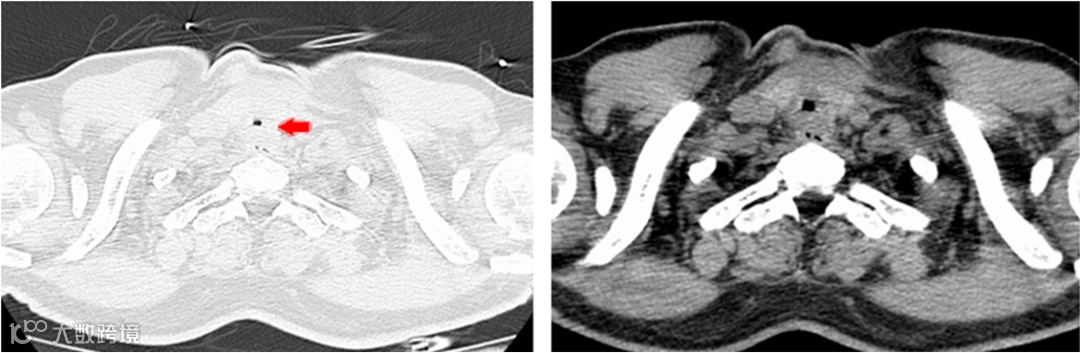

阿德入院时的颈部CT

可见气管重度狭窄

该患者气道狭窄为化学损伤加切开后机械损伤功能所致,且狭窄位置较高,距离声门仅2cm,这种气道狭窄的处理非常棘手,风险高,技术难度大。呼吸与危重症医学科关巍主任迅速申请全院MDT。医院领导高度重视,由朱燕辉副院长主持,医务科黄志浩主任积极协调,麻醉科、ICU、影像科等科室积极参与,针对患者病情制定了个体化手术方案,并在麻醉科的全力配合下,完成了:喉罩全麻下经支气管镜电凝+冷冻+球囊扩张+局部曲安奈德喷洒治疗。